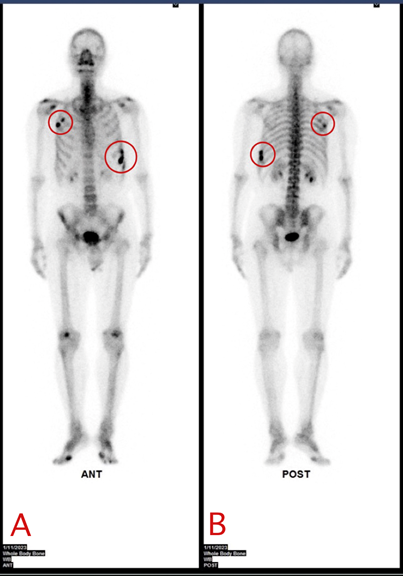

Patient, a 56-year-old man, had a car accident with hitting against his chest wall on November 13, 2022, and afterward, he felt pain at the right-sided chest wall. He went to the ER of our hospital, where all the examinations including plain X-ray films did not show any abnormalities in the rib cage. However, pain took place at the left-sided chest wall since December 2, 2022, which worsened since December 5, 2022, when the patient lift a heavy briefcase at work. Since then, every time the patient felt chest wall pain when he coughed, bent over, or woke up in the morning. On December 10, 2022, the patient visited our rehabilitation clinic, where the physical examinations reveal local tenderness of the chest wall in the both sides. We arranged the skeletal scintigraphy for early detection, which shows increased uptake (hot spot) over the anterior right 4-5th ribs and lateral left 8-10th ribs (Figure 1). The hybrid images with SPECT/CT scan show exact abnormality at the each corresponding positions (Figures 2-6). The diagnosis of hairline fracture of ribs, right ribs 3-4th and left ribs 8-9-10th was made. The patient then received non-steroidal anti-inflammatory drug (Voren-G gel, 10 MG/G 40G, TID) for one month and got treated by rehabilitation modalities, such as low-level laser therapy (LLLT) and transcutaneous electric nerve stimulation (TENS) at the chest wall (right upper part + left lower part), six times a month. The chest wall pain completely resolved in two months.

Figure 1 Whole body bone scan of the case. A, B is the final radioactivity image when the Tc-99m MDP was injected intravenously 3 hours later. A is anterior and B is posterior. The red circles depict the abnormal uptake of radiotracers, which can be seen at right upper ribs and left lower ribs.